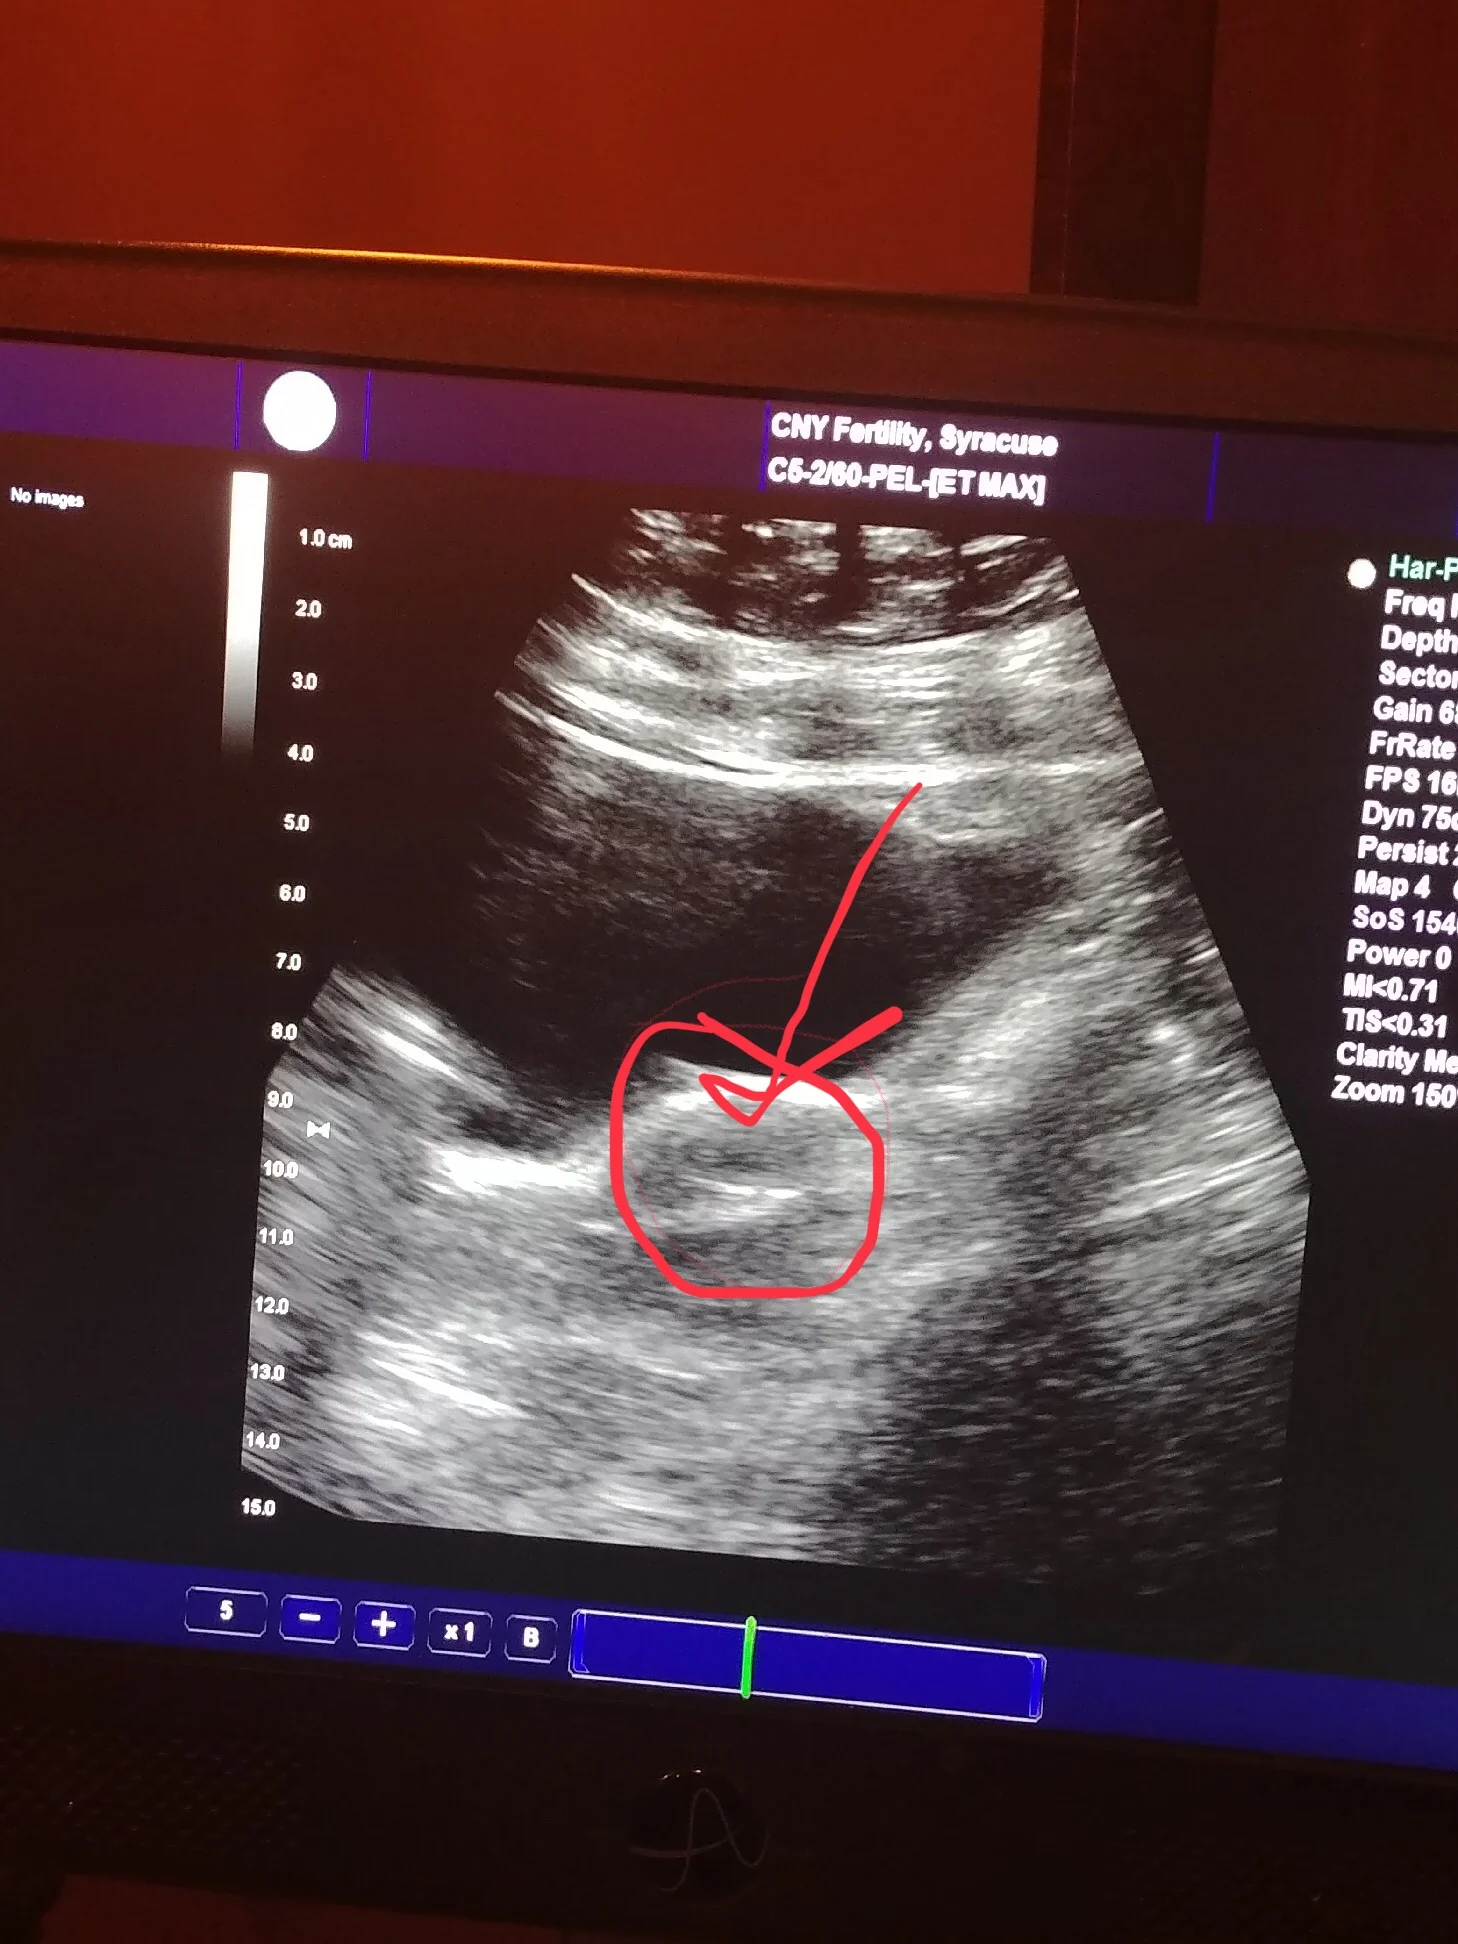

The protocol for IVF is not an easy one. A surrogate changes her daily routine, injects hormones, and fills her body with steroids and other medications, all in the hopes to make her womb a welcoming environment for someone else’s baby. The doctor does the transfer, but the embryo has to implant itself. We learned that our teeny tiny embryo miracle implanted on March 8, 2019! The weeks that followed were filled with continued hormone injections, other necessary medications, and weekly ultrasounds and bloodwork. Emerald took it all in stride. She is the embodiment of strength and compassion. She is a strong, brave woman, and the best auntie ever! She is giving us such an incredible gift, for which we will be eternally grateful.